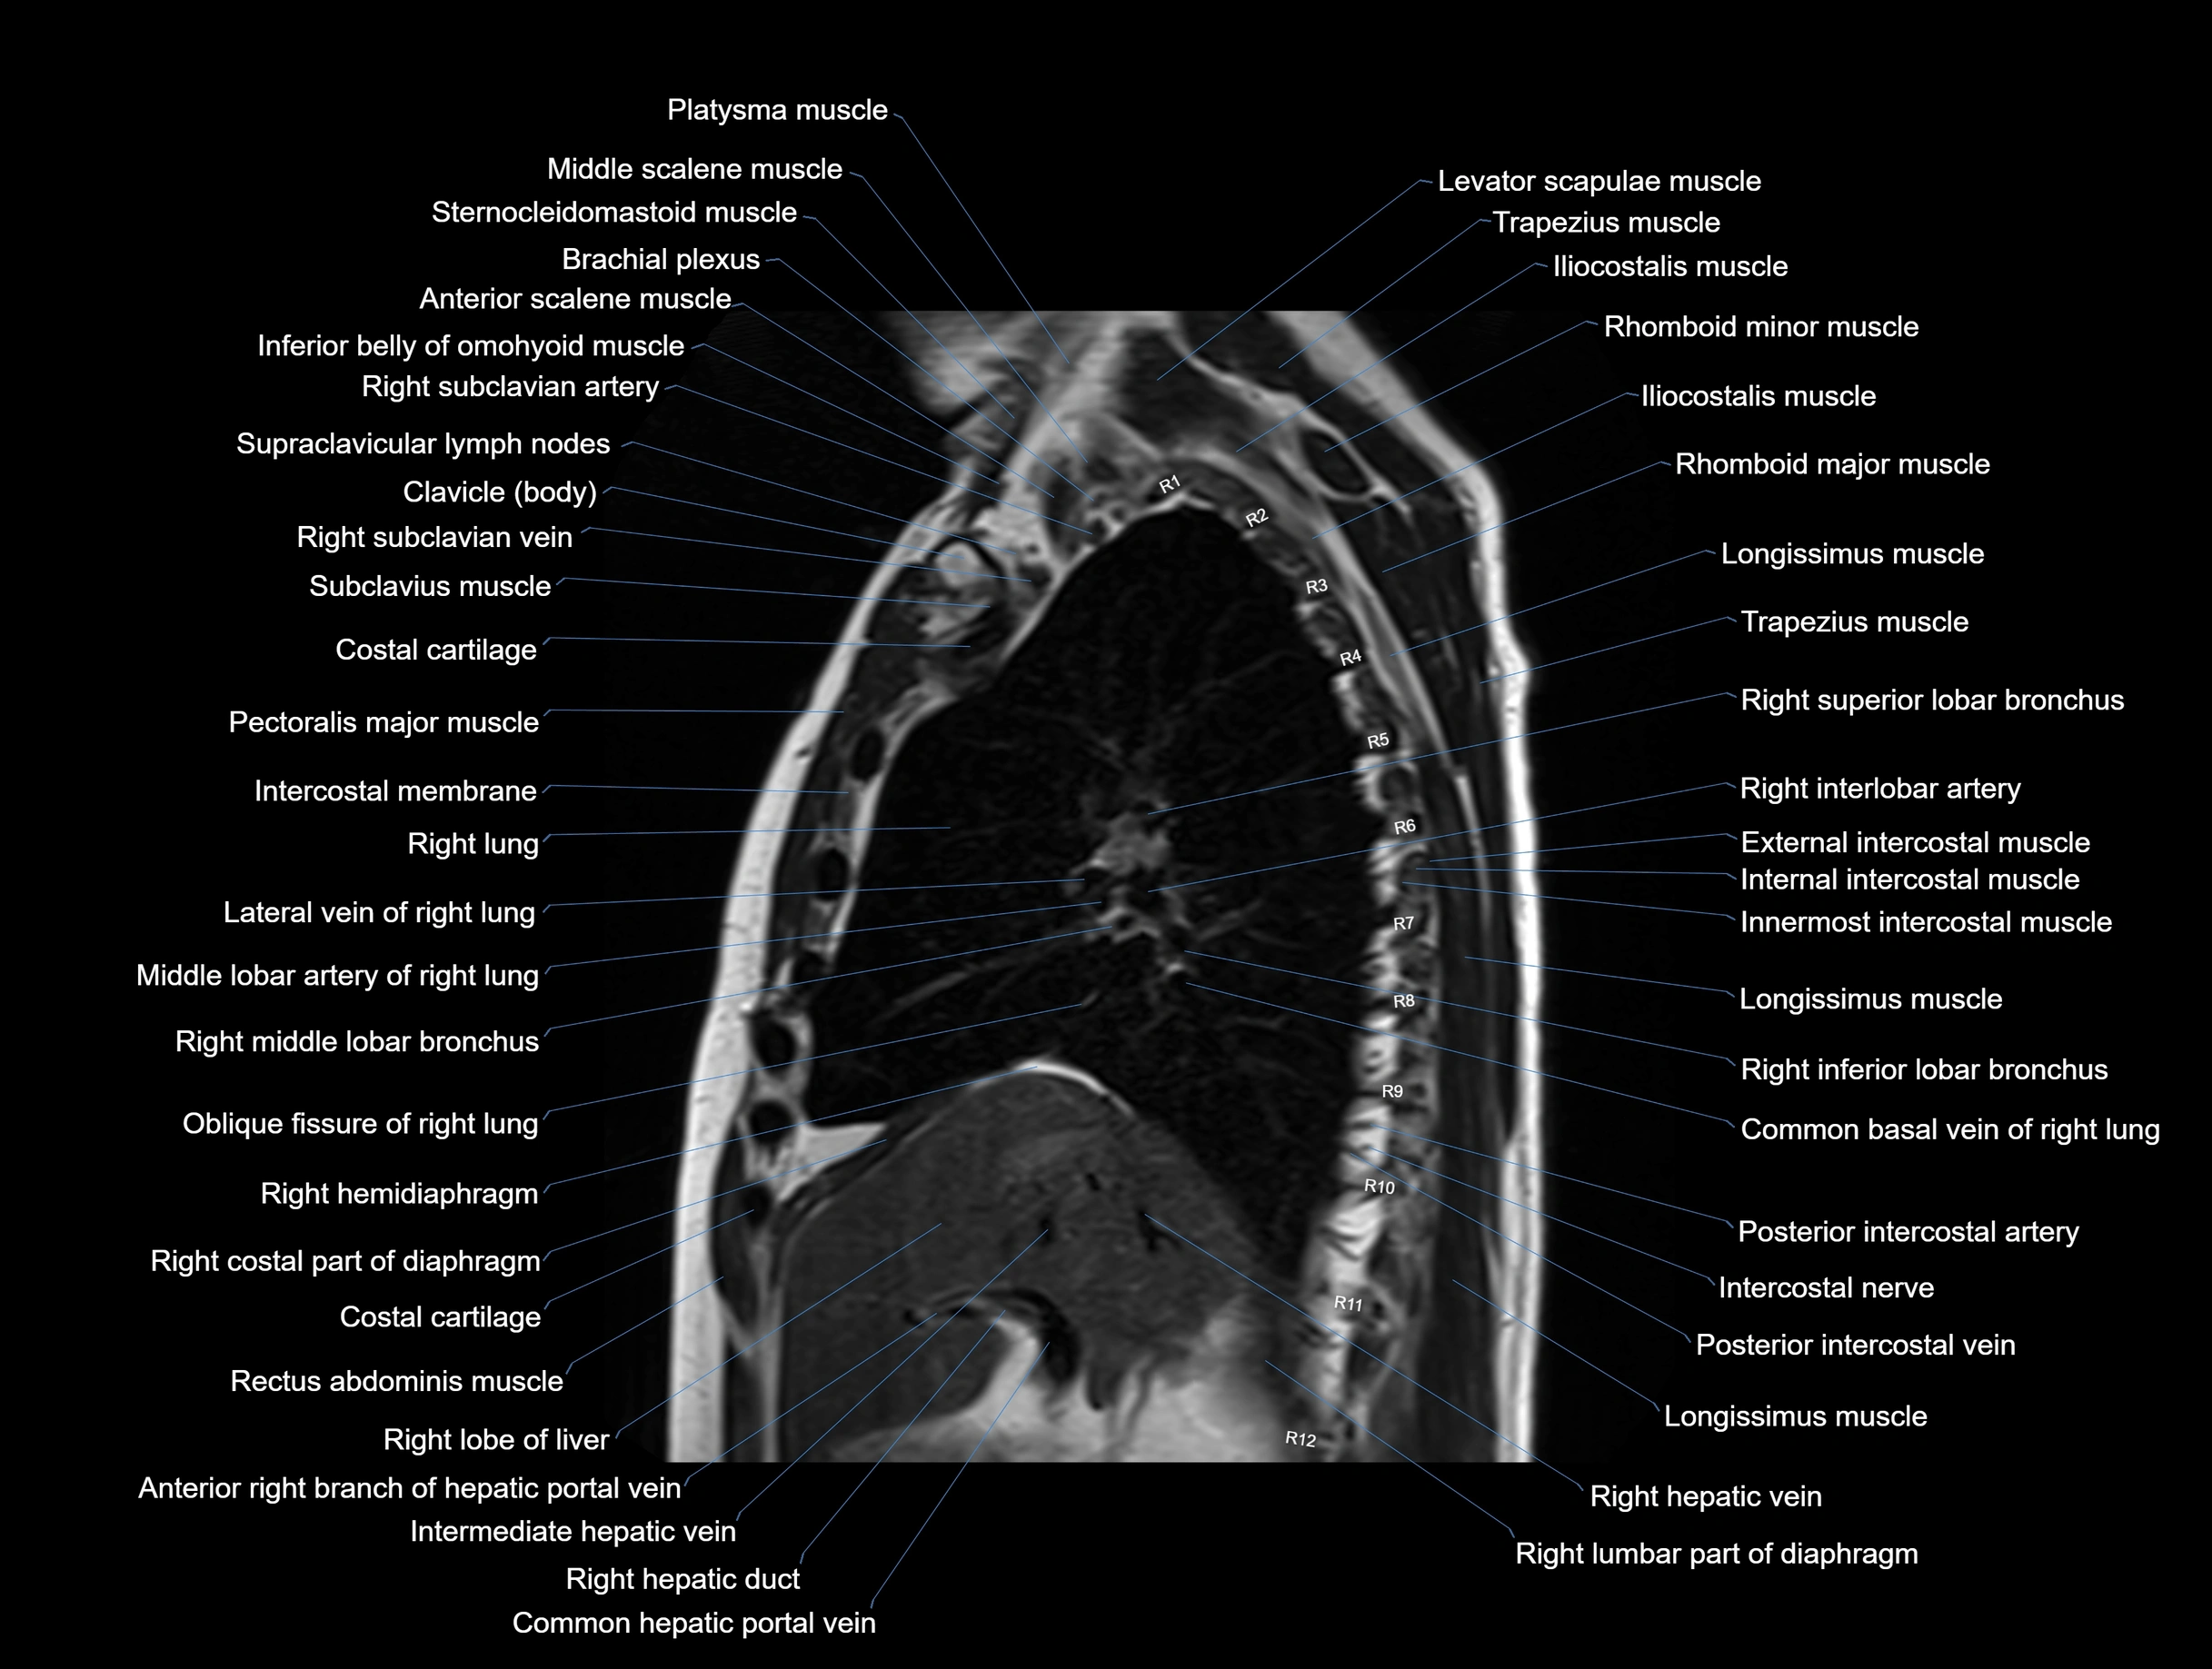

MRI images